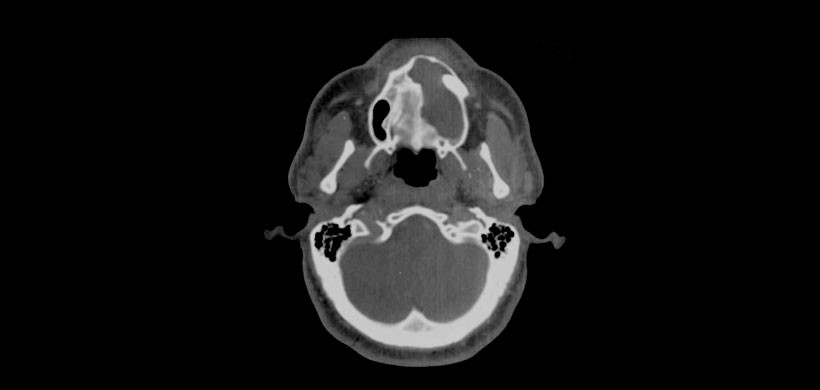

Radiográficamente, el quiste odontogénigo glandular aparece como una lesión radiolucida uni o multilocular. (Fig 1) Desde 1987, sólo 51 casos de estos quistes han sido bien documentados radiográficamente en la literatura inglesa.

Radiográficamente, el 52% de las lesiones eran uniloculares y el 48% eran multiloculares; el 94,5% mostró bordes bien definidos. La información sobre la integridad de la cortical estaba disponible en sólo 24 casos: 50% mostró una perforación, un 8,3% erosión de las corticales y 8,3% adelgazamiento de estas mismas. (Fig 2) En cuanto a la reabsorción radicular se encontró en un 22% y en un 24% el desplazamiento de los dientes.(Fig 3)